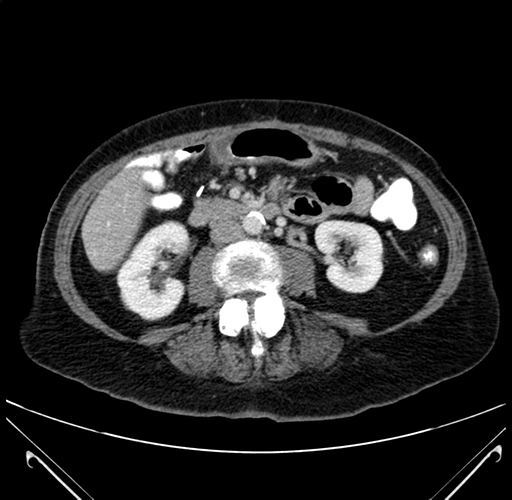

Pre-Chemo: Axial Venous

Axial Venous